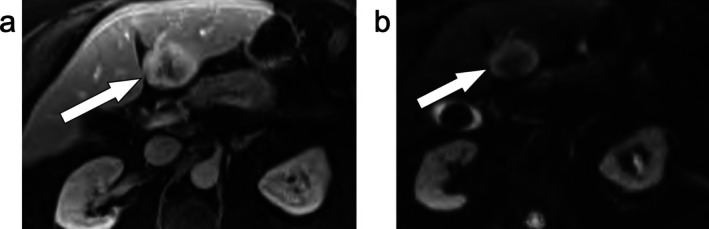

美国放射学会肝脏影像学报告和数据系统(LI-RADS)是对肝细胞癌高危患者肝脏影像学观察进行分类和风险分层的卓越框架。本文综述了肝细胞癌的发病机制和MRI在LI-RADS中的应用,具体包括LI-RADS诊断算法,其组成部分,以及参考最新支持证据的可重复性。综述了LI-RADS治疗反应算法,包括最近的放射治疗反应算法。探讨了人工智能的应用,争议点,LI-RADS相对于其他肝脏成像系统,以及可能的未来方向。通过阅读本文,读者将对LI-RADS的基础和应用以及可能的未来方向有一个了解。

The American College of Radiology Liver Imaging Reporting and Data System (LI-RADS) is the preeminent framework for classification and risk stratification of liver observations on imaging in patients at high risk for hepatocellular carcinoma. In this review, the pathogenesis of hepatocellular carcinoma and the use of MRI in LI-RADS is discussed, including specifically the LI-RADS diagnostic algorithm, its components, and its reproducibility with reference to the latest supporting evidence. The LI-RADS treatment response algorithms are reviewed, including the more recent radiation treatment response algorithm. The application of artificial intelligence, points of controversy, LI-RADS relative to other liver imaging systems, and possible future directions are explored. After reading this article, the reader will have an understanding of the foundation and application of LI-RADS as well as possible future directions.